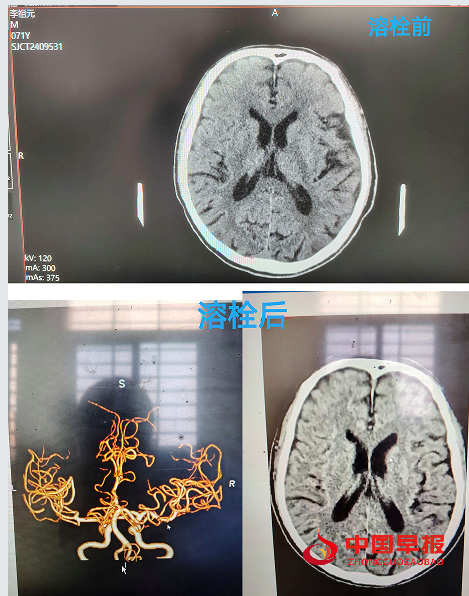

当天下午13时许,沈集镇雨林村的李爷爷在家中突发口角歪斜、言语含糊、左侧肢体无力,家属发现后,迅速将其送至沈集镇中心卫生院急诊室内,争分夺秒的战斗悄然打响,医护人员迅速启动“脑卒中绿色通道”。经过一系列检查,确诊患者为急性脑卒中且处于溶栓时间窗内,时间就是生命,医护人员立即对患者实施静脉溶栓治疗,治疗过程中,医护人员紧密配合,紧盯老人各项生命体征的细微变化,确保每一个环节都精准无误。溶栓后,患者生命体征稳定。为进一步巩固治疗效果,老人被转送至上级医院进行后续治疗,1小时后,经上级专家反馈患者状态明显好转,溶栓效果良好。